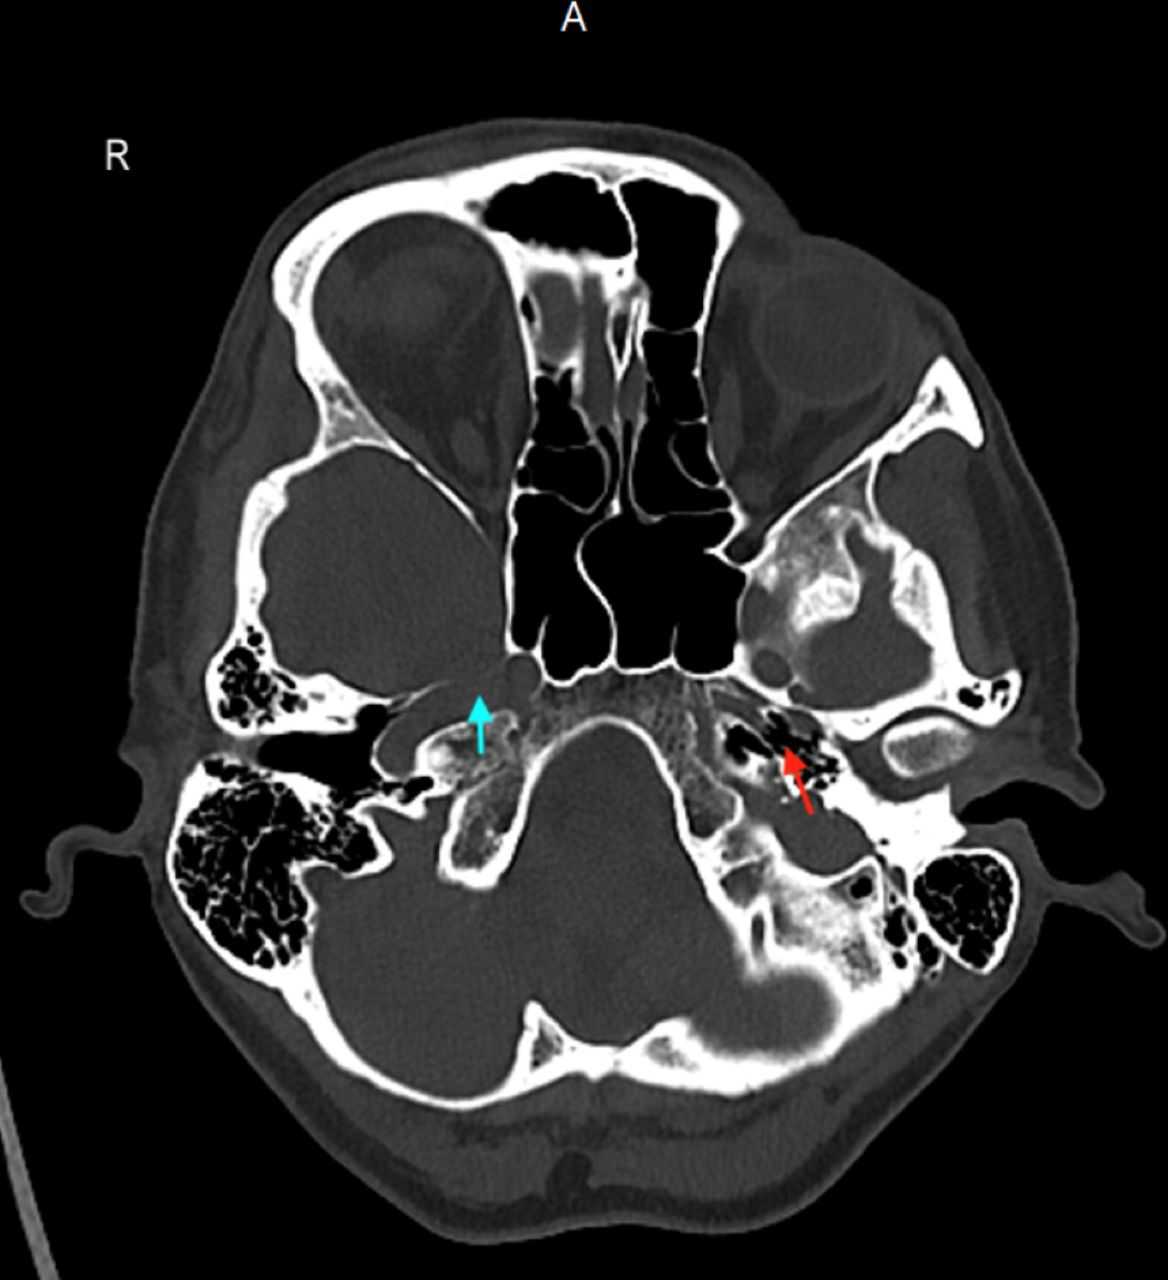

Компьютерная томография головы не выявила острой внутричерепной патологии, однако показала полное отсутствие левого шейного и пещеристого сегментов внутренней сонной артерии, а также гипоплазию (недоразвитие) левого сонного канала, что подтверждало врожденное происхождение аномалии. Коллатеральное кровообращение сохранялось за счет левой задней соединительной артерии и единственной передней мозговой артерии. Дуплексное ультразвуковое исследование сонных артерий подтвердило отсутствие левой внутренней сонной артерии.